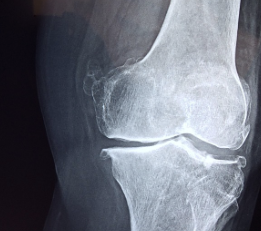

1. 퇴행성 관절염

원인: 관절 연골의 손상으로 인해 발생하며, 주로 노화와 관련이 있습니다.

증상: 오래 걷거나 서 있을 때, 계단을 오르내릴 때, 쪼그려 앉을 때 통증이 심해집니다. 밤에 통증으로 잠을 자기 어려울 수 있습니다.

퇴행성 관절염은 관절 연골의 점진적인 소실로 인해 발생하는 가장 흔한 관절 질환입니다.

주로 50세 이후에 발병하며, 여성에게 조금 더 높은 확률로 나타납니다.

▶ 노화, 비만, 과도한 관절 사용, 반복적인 외상 등이 원인이 될 수 있습니다.

▶ 아침 증상은 거의 없거나 15분 이내로 지속됩니다.

▶ 움직일수록 통증이 심해지며, 오전보다 오후에 더 심한 경향이 있습니다.

▶ 주로 무릎, 골반, 척추 등 체중을 지탱하는 관절에 영향을 미칩니다.